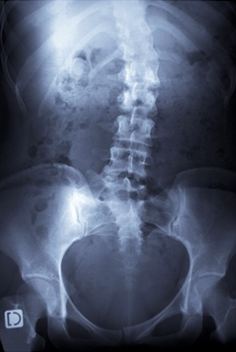

Si une déformation du dos existe lors de l’examen clinique et qu’une scoliose est suspectée, des radiographies permettent généralement de confirmer le diagnostic et, surtout, d’évaluer son importance.

© 123RF-Laurent Dambies

Il ne s’agit pas de radiographies standard, mais de grand « clichés » spécialisés prenant l’ensemble de la colonne vertébrale, cervicale, dorsale et lombaire, ainsi que le bassin, de face et de profil : c’est la « téléradiographie », que l’on appelle parfois le « grand cliché dorso-lombo-pelvi-fémoral ». C’est à partir de ces radiographies que peuvent être mesurée les angulations des vertèbres entre elles (« angle de Cobb »).

Il s’agit de l'angle formé à partir de l'intersection de deux droites tangentielles l'une au plateau supérieur de la vertèbre supérieure la plus déviée par rapport à la verticale (vertèbre « limite »), l'autre au plateau inférieur de la vertèbre inférieure la plus déviée par rapport à la verticale (vertèbre limite inférieure).

Les radiographies permettront aussi de suivre l’évolution des déformations de la colonne vertébrale grâce à la répétition des mesures de ces déformations et de cet angle de Cobb.